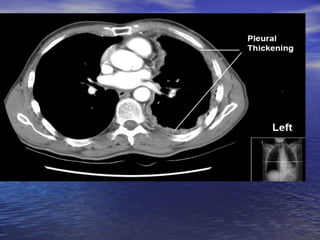

CT CHEST AFTER 10 DAYS

CT CHEST AFTER 10 DAYS RIGHT HYDROPNEUMOTHORAX EMPHYSEMATOUS BULLAE IN B/L LOWER LOBE, RIGHT MIDDLE LOBE B/L LOWER LOBE BRONCHIECTASIS

CT CHEST AFTER10 DAYS RIGHT HYDROPNEUMOTHORAX EMPHYSEMATOUS BULLAE IN B/L LOWER LOBE, RIGHT MIDDLE LOBE B/L LOWER LOBE BRONCHIECTASIS